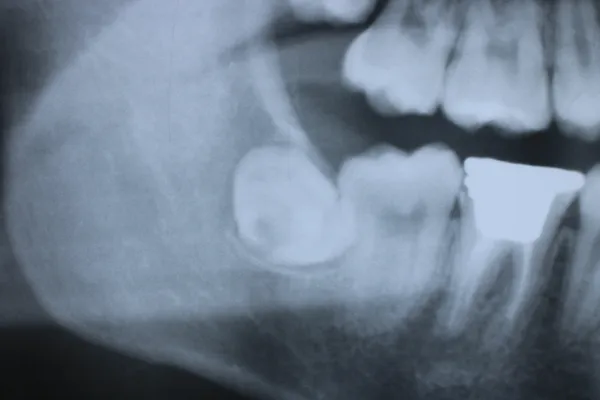

7親知らず

Case8